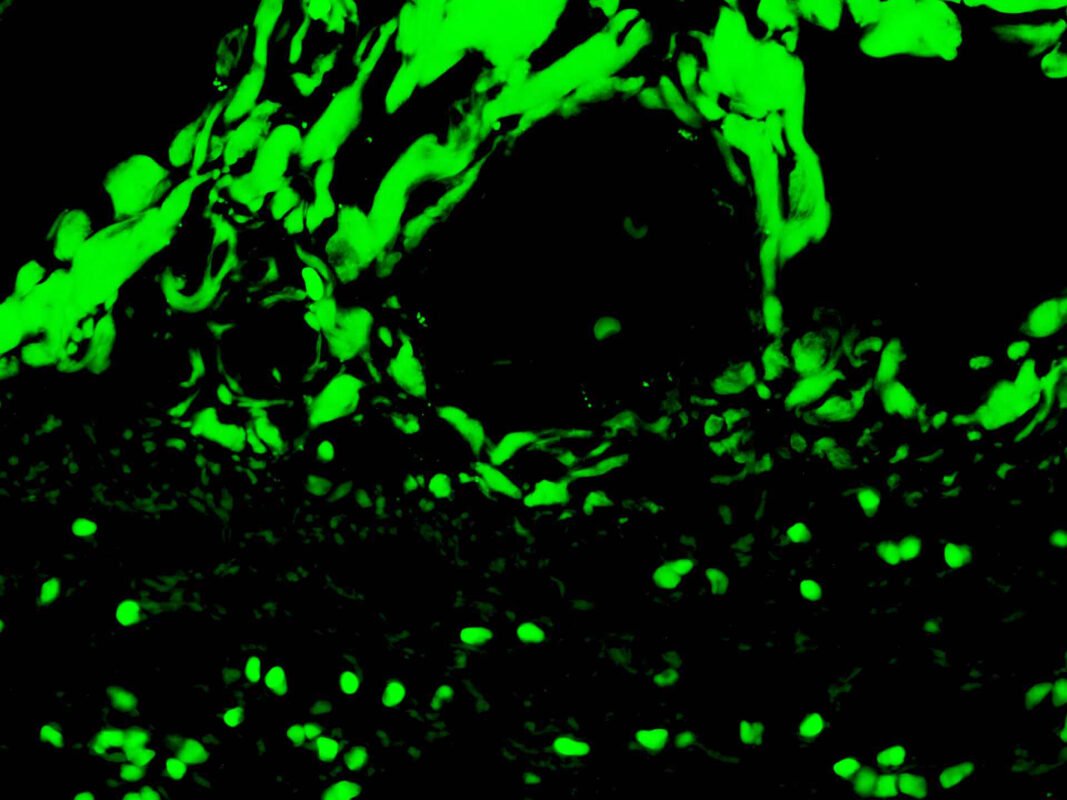

C3c Complement-FITC

Complement component 3 (C3) is a critical protein in the immune system, forming a key part of the

complement cascade and innate immunity.

• C3 glomerulopathy describes kidney conditions where C3 deposits accumulate in the glomeruli

without significant immunoglobulin presence, hinting at alternative complement pathway

activation.

• Lupus nephritis involves kidney inflammation due to Systemic Lupus Erythematosus (SLE) and

typically shows immunofluorescent positivity for IgG, IgA, IgM, C3, and C1q.

VisualisationCytoplasmic and Membranous